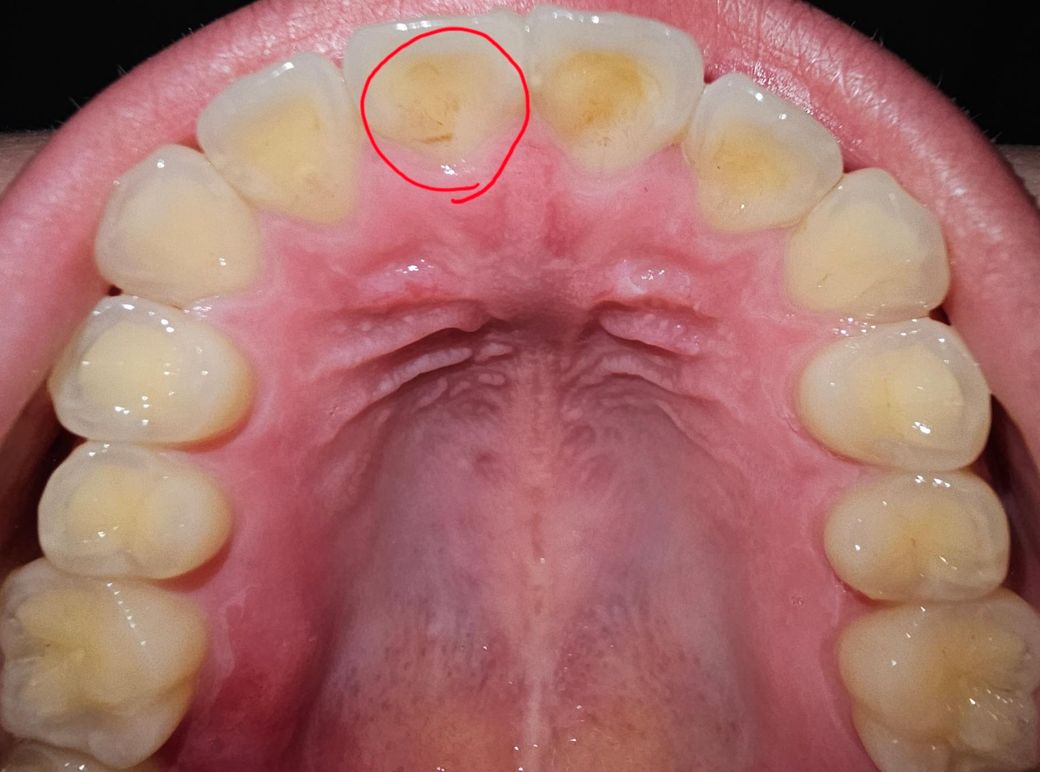

앞니가 시립니다. 충치인지 치석인지 궁금합니다.

어제부터 갑자기 찬물(아주 차가운 물이긴 합니다)을 마시면 딱 사진 속 표시한 앞니가 시립니다. 사진을 찍어보니 갈색이 보여서 그런데... 충치일까요? 아니면 치석인가요?

충치때문에 치아가 시린거 같진 않고 양치가 안되서 잇몸염증때문에 시린거 같으니 치과에 가셔서 스켈링을 먼저 받아보세요.

1. 충치는 아니고 치석 같습니다

2. 스케일링 받아보세요